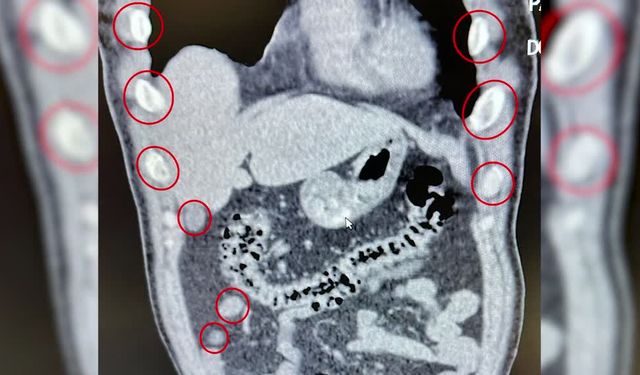

Bitlis'te mide ve bağırsaklarında uyuşturucu tespit edildi: Tutuklandılar